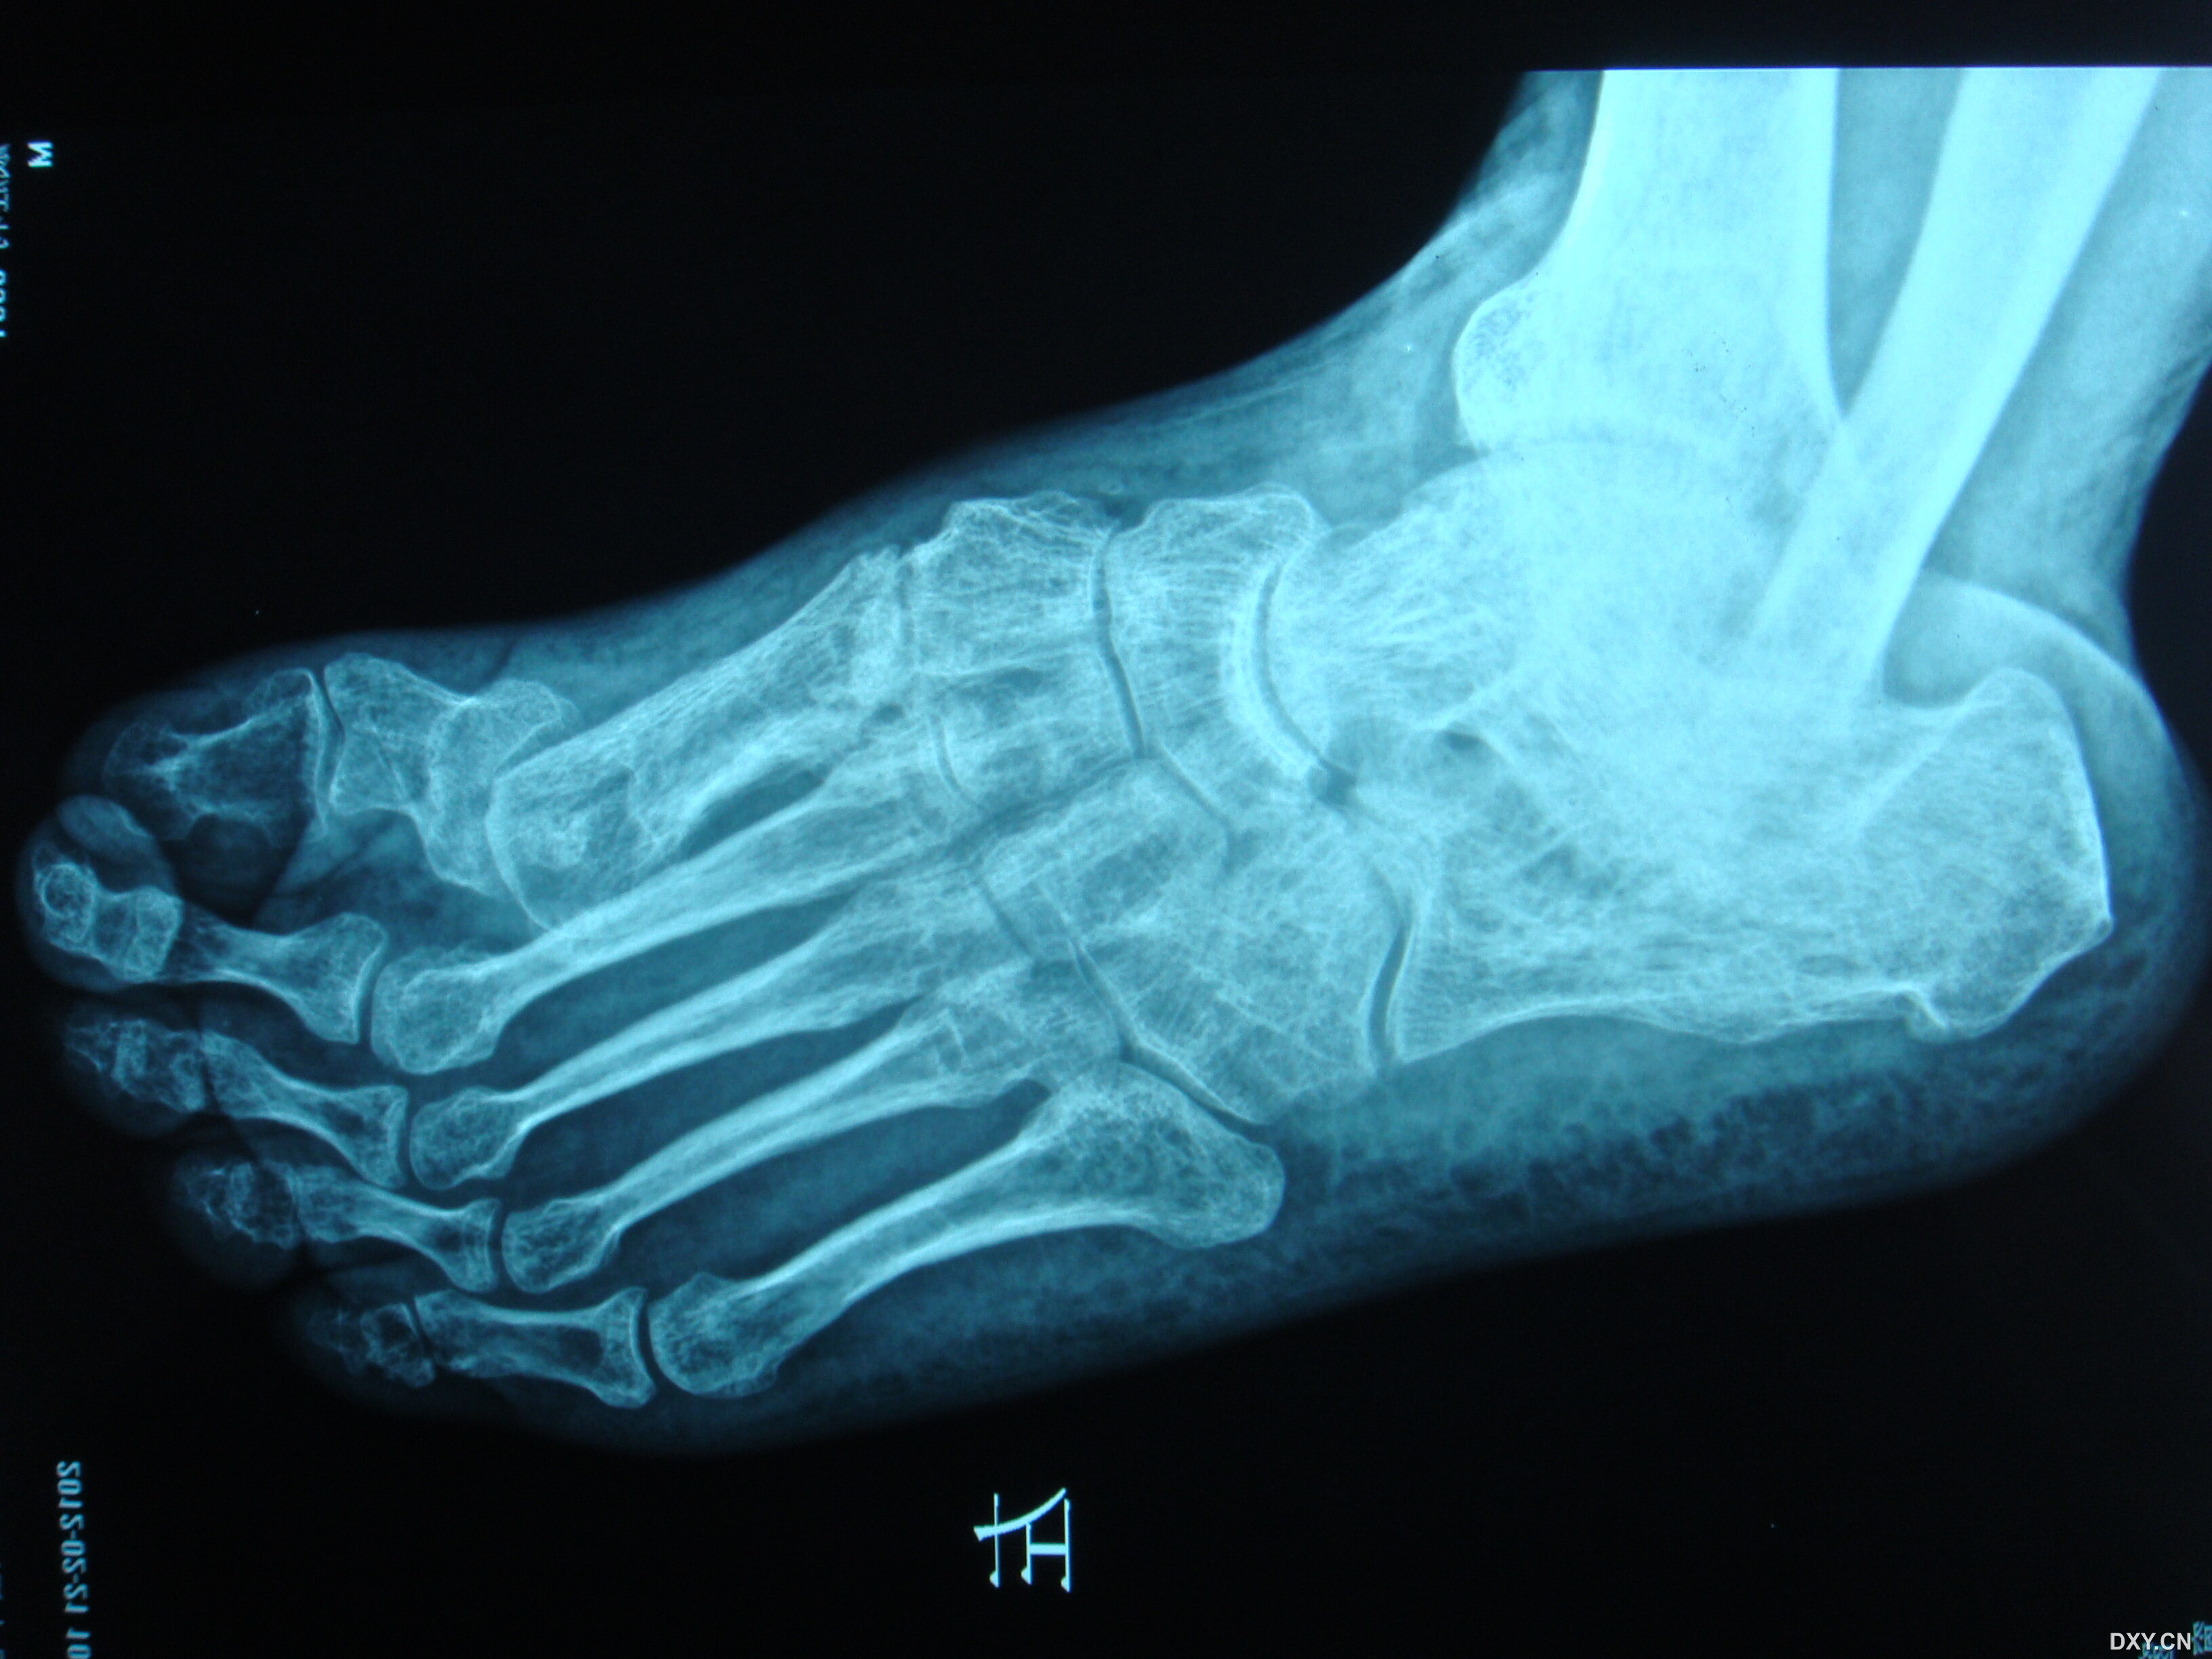

第一跖骨陈旧性骨折畸形愈合 - 骨科专业讨论版 -丁香园论坛